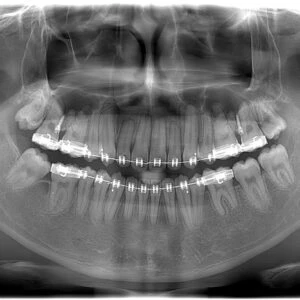

Sâu răng là một vấn đề phổ biến và thường xảy ra ở trẻ. Đây là một tình trạng mà men răng bị phá huỷ do tác động của axit tiếp xúc với men từ vi khuẩn trong miệng. Sâu răng không chỉ gây đau đớn và khó chịu cho trẻ, mà còn có thể ảnh hưởng tiêu cực đến chất lượng cuộc sống, sức khỏe.

Giai đoạn từ 5 – 10 tuổi ở trẻ là thời điểm dễ bị sâu răng nhất là răng sữa. Do trẻ nhỏ thường không vệ sinh răng miệng đúng cách và thường ăn các loại thực phẩm ngọt kèm nước uống có ga, tạo môi trường tốt cho vi khuẩn phát triển.